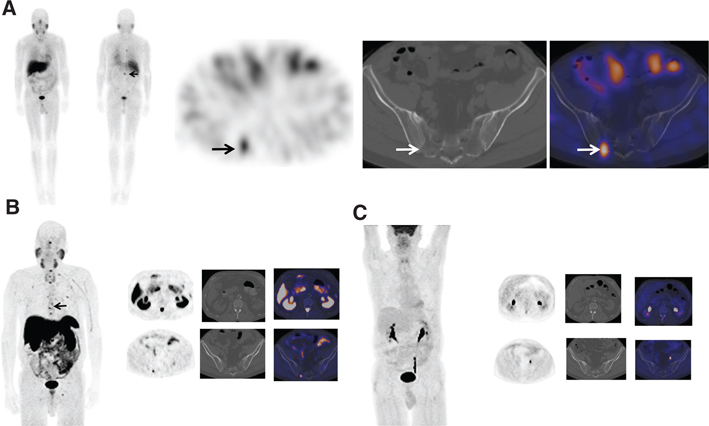

Ga-68 DOTATATE, with affinity to SSTR 2 and 5, was approved for use by the FDA in June 2016 (NETSPOT®).68 Ga-DOTATATE is indicated for localization of SSTR-positive NETs in both adults and children. Typical normal biodistribution is uptake in the pituitary, thyroid, adrenals, liver, spleen, uncinate process of pancreas, kidneys, and bladder. The method of evaluation is similar to octreoscan. Focal increased activity, not typical of normal distribution, is suspicious for disease (Figures 8 and 9). Similar to In-111 pentetreotide, false-positive findings can be seen and misinterpreted, and it is important to be aware of normal distribution and variants. No set diagnostic criteria currently exist for DOTATATE imaging, although there has been a proposal to standardize the reporting criteria using a 5-point structured system (54).

Fig 8

Figure 8 A 60-year-old woman with familial paraganglioma/pheochromocytoma syndrome status after right adrenalectomy with increased plasma metanephrine levels. (A) Previous whole body planar I-123 MIBG scan with attenuation-corrected SPECT, CT, and fused SPECT/CT images show increased uptake in multiple osseous lesions (white arrows). The patient was subsequently treated with I-131 MIBG therapy. (B) Ga-68 DOTATATE PET/CT maximum intensity projection (MIP) image of the skull vertex to the proximal thigh performed 5 years post-therapy because of increasing tumor markers shows widespread somatostatin receptor-positive bone metastatic disease with marked tracer uptake (arrows). (C) An F18-FDG PET/CT performed 1 week prior showed minimal to no uptake in corresponding osseous lesions.

Fig 9

Figure 9 A 55-year-old woman with metastatic paraganglioma having an initial Ki67 proliferation index of 25% and strong SSTR2A immunostain but without SDHB mutation on germline testing. (A) Ga-68 DOTATATE PET/CT maximum intensity projection (MIP) images of the skull vertex to the proximal thigh on the left show widespread somatostatin receptor-positive metastatic disease, with progressive disease on the right image with enlarging pelvic osseous lesions (arrows). (B) Ga-68 DOTATATE PET/CT axial fused PET/CT, axial PET, and sagittal fused PET/CT images show enlarging vertebral lesion (arrows) on the current study (top images) as compared to the prior (bottom images).